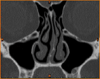

Coronal view showing leftward septal deviation.